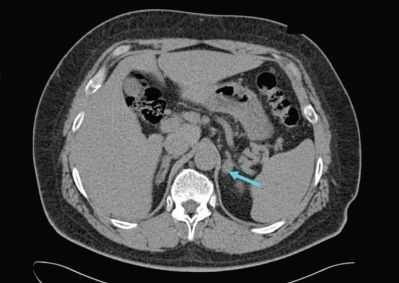

Для пациентов с доказанным первичным гиперальдостеронизмом следующим шагом является выяснение, каким заболеванием он вызван, — односторонним или двусторонним. Это очень важно, так как лечение каждого из них отличается. Компьютерная или магнитно-резонансная томография позволяют увидеть, есть ли опухоль в надпочечнике. Если пациент младше 40 лет и у него есть опухоль только в одном надпочечнике, то в этом случае можно приступать к лечению. Если пациент старше 40 лет и/или у него либо нет опухоли, либо есть опухоль, но в обоих надпочечниках, то возникает необходимость в проведении специального теста — селективного забора венозной крови из центральной вены надпочечников. В ходе этого теста хирург или рентгенолог берёт кровь непосредственно из вен обоих надпочечников, чтобы определить, какой именно орган вырабатывает патологическое количество гормона.

УЗИ надпочечников — низкочувствительный метод диагностики. Предпочтительнее проводить КТ: она помогает выявить как макро- и микроаденомы надпочечников, так и утолщения ножек надпочечников, гиперплазии и другие изменения [14] .

Для уточнения формы гиперальдостеронизма (одностороннего и двустороннего поражения) проводится селективный забор крови из вен надпочечников в специализированных центрах [9] . Это исследование эффективно снижает риск необоснованного удаления надпочечника только по данным КТ [4] .